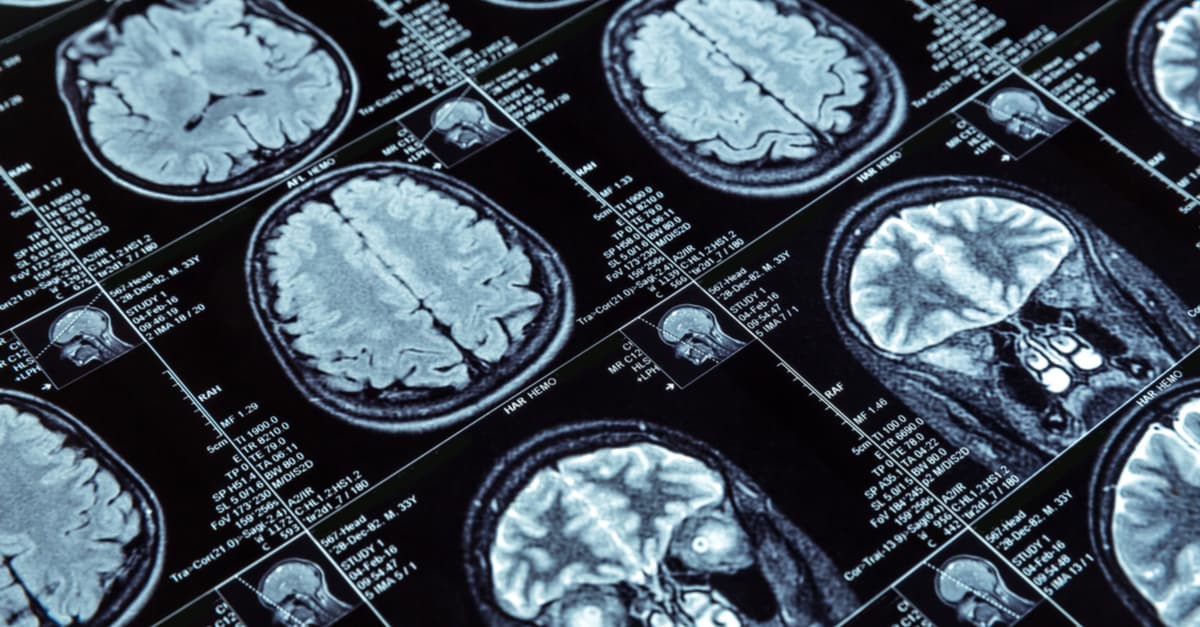

Parnia señala que la parte pensante del cerebro, llamada corteza, se desacelera rápidamente cuando el corazón deja de latir, debido a que su funcionamiento depende del sistema cardiorespiratorio. Generalmente, las ondas cerebrales desaparecen de los monitores en un período que va desde los 2 a los 20 segundos. Cuando las ondas se vuelven planas, el paciente es considerado oficialmente fallecido.

Parnia se centra en un caso que se dio en Canadá, en donde un paciente mostró actividad cerebral persistente hasta 10 minutos después de que apagaran la máquina que lo mantenía vivo. En este caso, la persona, que estaba clínicamente muerta, contó con ondas cerebrales similares a las de una persona que duerme, hasta 10 minutos después de la muerte.

Por otra parte, la investigación descubrió que cada paciente muestra registros electroencefalográficos diferentes después de la muerte. La conclusión de la investigación del Dr. Parnia es que, aunque la sangre no continúa llegando al cerebro, las personas aún guardan un cierto nivel de consciencia. Es decir que, aunque técnicamente una persona está muerta, su cerebro puede seguir funcionando.